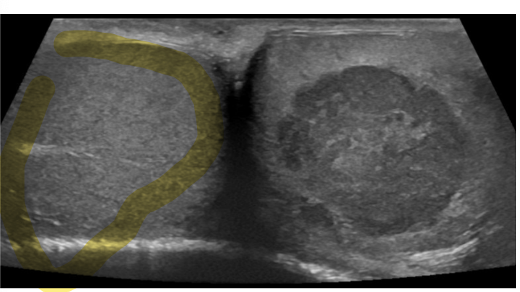

What is this?

Testicular ultrasound